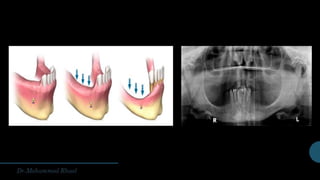

Anatomical considerations